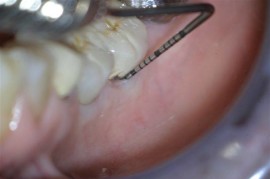

LASER Treatment of Failing Implant

Pocket depth was reduced from 7mm to 3mm. Note also that the gingiva no longer bleeds upon probing.